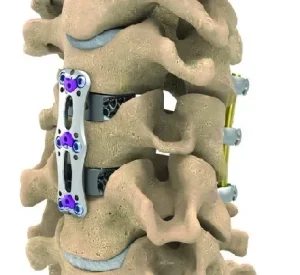

Anterior cervical plate & Anterior Cervical Inter body Spacer dealers in Ahmedabad

- It is indicated in degenerative disc injuries, trauma, and tumor, to treat deformities, stenosis, and spondylolisthesis.

This Anterior Cervical Plate is generally used for providing support to the spinal cord during the surgery or the anterior cervical discectomy and fusion (ACDF) procedures. This plate also plays an important role in bone grafting.

While fixing this Anterior Cervical Plate the doctor makes use of the MRI, X-rays, or the CT scan technique to ensure that they are placed and fixed properly.